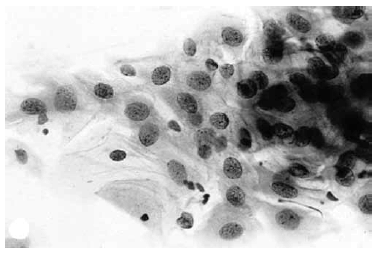

Nas questões de números 46 a 60, assinale a alternativa que melhor corresponde ao diagnóstico do quadro microscópico apresentado.